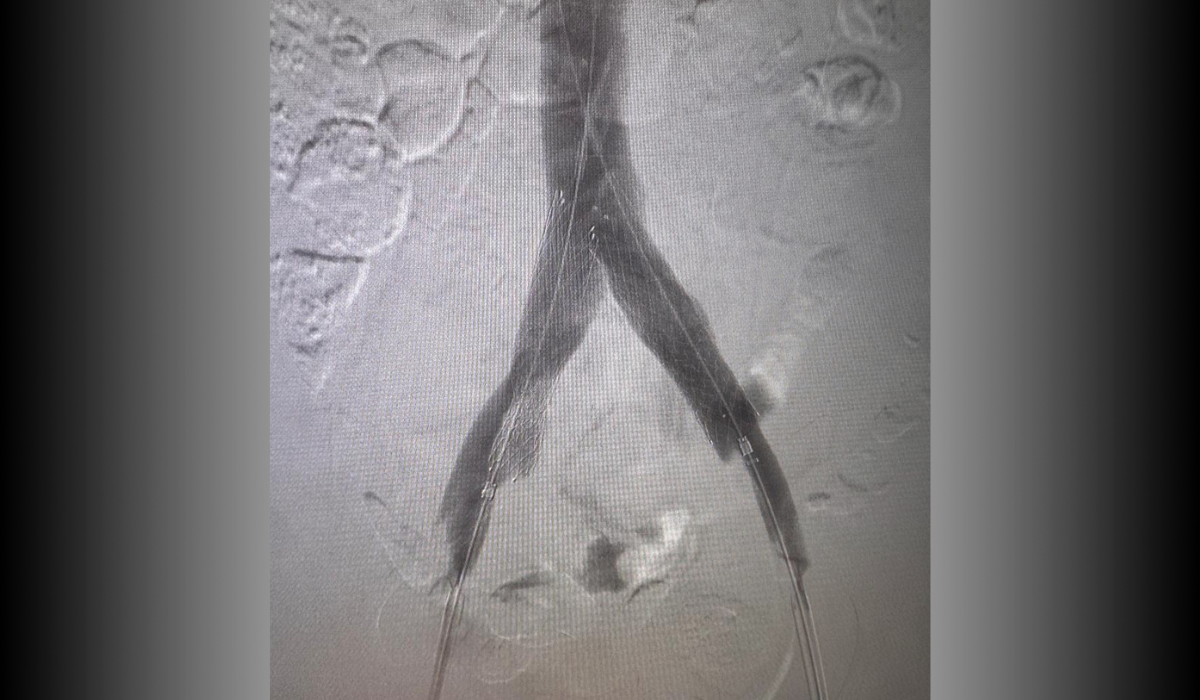

Antes: Oclusión bilateral ilíaca

Antes

Oclusión de ambas venas ilíacas/Sindrome de congestión pélvica

Después: Reconstrucción con stents

Después

Reconstrucción con stents. Flujo normalizado y resolución clínica.